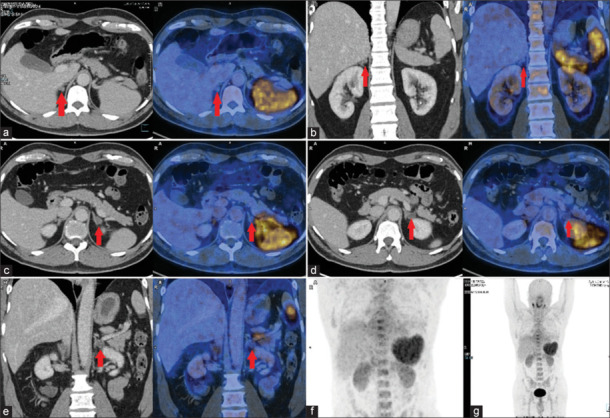

原发性醛固酮增多症(Primary aldosteronism, PA)是继发性高血压的常见病因之一,其特点是醛固酮自主分泌过多,同时肾素抑制。通过手术治疗的PA患者的临床和生化缓解率远高于通过药物治疗的患者;因此,亚型PA对于确定哪些患者将从手术中获益最大至关重要。计算机断层扫描(CT)扫描与肾上腺协议和肾上腺静脉采样(AVS)是常用的PA亚型分类。CT扫描是结构成像,不能提供功能信息,而AVS是一种侵入性的、技术上具有挑战性的方法,成功率有限,并发症风险高。C-X-C趋化因子受体4型(CXCR4)在醛固酮产生组织中过表达,但在无功能腺瘤中的表达几乎可以忽略不计。正电子发射断层扫描示踪剂68ga - pentxafor是CXCR4的特异性配体,可无创检测醛固酮产生性腺瘤,指导手术治疗。下面的图像系列展示了ga -68- pentxafor对PA亚型诊断的效用和结果模式。

Primary aldosteronism (PA) is one of the prevalent causes of secondary hypertension, characterized by the autonomous hypersecretion of aldosterone and concurrent renin inhibition. Clinical and biochemical remission rates for patients with PA achieved through surgery are far higher compared to those achieved through drug treatment; hence, subtyping PA is crucial for identifying patients who will benefit most from surgery. Computed tomography (CT) scan with adrenal protocol and adrenal venous sampling (AVS) is used conventionally for PA subtype classification. CT scans, being structural imaging, cannot provide functional information, while AVS is an invasive, technically challenging method with a limited success rate and a high risk of complications. The C-X-C chemokine receptor type 4 (CXCR4) is overexpressed in aldosterone-producing tissue but is almost negligibly expressed in nonfunctional adenoma. The positron emission tomography tracer 68Ga-pentixafor, a specific ligand for CXCR4, can detect aldosterone-producing adenoma noninvasively, which can guide surgical treatment. The image series below demonstrates the utility and patterns of findings on Ga-68-pentixafor for subtyping PA.